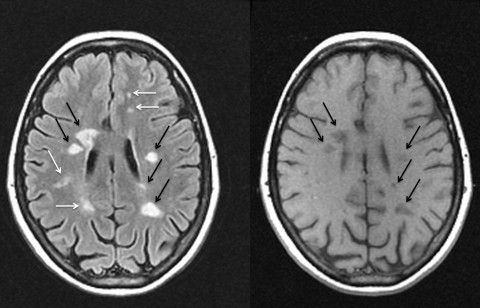

AM FM Based Prediction Of Multiple Sclerosis In Brain MRI Images

AM FM based Prediction of Multiple Sclerosis in Brain MRI Images S.P.Washimkar Asst. Professor Electronics & Telecommunication Engg Dept. PCE, Nagpur (some scattered bright spot) on the MRI, their location and their size. ... Access Document